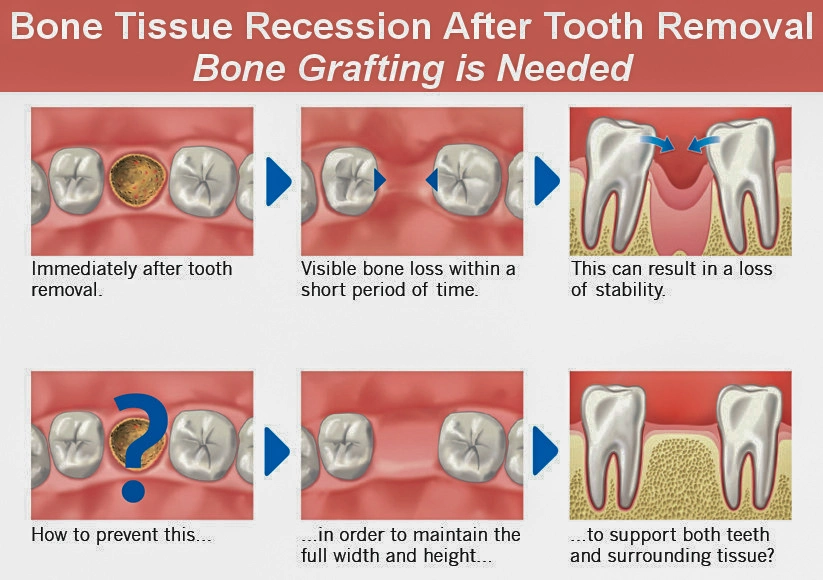

Why Do Some Implant Cases Require Bone Grafting?

Bone loss doesn’t announce itself — it progresses quietly.

Common causes include:

- Tooth loss months or years ago

- Gum (periodontal) disease

- Old infections or failed dental work

- Natural bone resorption over time

- Accidents or trauma

Without reinforcement, implants placed in these conditions can lose stability or fail early.

Bone grafting removes that uncertainty and turns doubt into design.